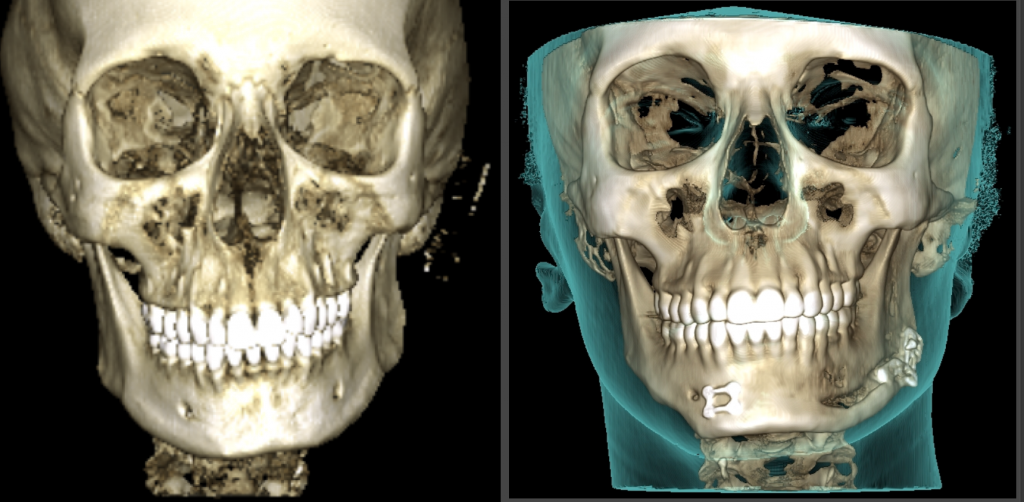

Découvrez les photos et le scanner avant/après pour observer l’évolution spectaculaire de ce cas de malformation oto-mandibulaire unilatéral Gauche.